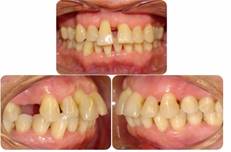

Tratamiento periodontal: La modalidad de tratamiento se presenta en la Tabla 1. El protocolo de tratamiento fue aprobado por el comité de ética de FOUCH y fue realizado bajo consentimiento informado. Se realizó instrucción de higiene oral con técnica de cepillado de barrido con cepillo de filamentos suaves, hilo dental y cepillo interproximal. El TP fue realizado por especialistas en periodoncia, con curetas periodontales Gracey y Mini-Five, ultrasonido, complementado con terapia antibiótica de amoxicilina 500 mg. + metronidazol 250 mg. por 7 días al final de los pulidos radiculares. La reevaluación se realizó a las 4 semanas desde el último pulido radicular. Se evaluó inflamación gingival y control de biofilm dental. Luego se citó en 3 meses para realización de periodontograma de salida. Se realizó retratamiento de sitios periodontales que no cumplían los requisitos de salud periodontal en periodonto reducido (sin o mínimo sangrado al sondaje, sin cálculo supra o subgingival, sin sacos periodontales >5mm). Luego de estar en condición de salud periodontal clínica, se dio el alta periodontal, para posteriormente ser citada a la Terapia de Soporte Periodontal (TSP) cada 3 meses. Luego de dos intervalos de TSP, en donde la paciente mantuvo la estabilidad periodontal obtenida en la fase etiológica, se deriva a TO (Figura 4).

Tratamiento de ortodoncia: Al finalizar la segunda TSP se inició el TO por especialistas. Se planificó un tratamiento ortodóncico no conservador, con exodoncia del diente 3.1 para solucionar el apiñamiento y proinclinación incisiva inferior, permitiendo corregir el overjet y overbite y adicionalmente, mantener las relaciones oclusales en los sectores laterales. Para ello se utilizaron aparatos fijos prescripción Roth 0,022” (brackets Balance, GAC®, EE. UU.) en ambas arcadas, con tubos de cementado directo en molares (Ovation, GAC®, EE. UU.). En los incisivos superiores se realizó una cementación estratégica de brackets, posicionándolos más hacia cervical, siguiendo el nivel óseo remanente, observado en la radiografía panorámica. En dientes con pérdida ósea, el centro de resistencia se desplaza apicalmente, lo que determina que al aplicar una fuerza el momento generado sea mayor. La cementación estratégica permite acercar los brackets al centro de resistencia de cada diente y con esto, disminuir el momento que se genera al aplicar una fuerza ortodóncica. En el resto de los dientes, los brackets se cementaron en forma convencional, en el centro de la corona clínica. La paciente fue citada a control cada 4 semanas. En la arcada superior, el primer arco utilizado fue un alambre twist flex 0,0175” con dobleces compensatorios en los incisivos según la posición de los brackets. Una vez corregidas las rotaciones, a los 3 meses de TO, se inicia la intrusión con arco de acero 0,014” llegando como máximo a un acero 0,016”. En cada control se modificaron gradualmente los dobleces compensatorios (menos de 1 mm.), para lograr la intrusión de las piezas extruídas (Figura 5). El uso de arcos de acero permite entregar fuerzas interrumpidas, que son aquellas que disminuyen a cero entre activaciones, lo que posibilita un período para la reorganización de los tejidos antes de volver a aplicar la fuerza. La alineación y nivelación inferior se obtuvo utilizando arcos de NiTi 0,012” y luego a los tres meses se pasó a un acero 0,014” por dos meses más. Para la retrusión y cierre de espacio de la exodoncia del incisivo, se usó un arco de acero 0,016” con ansas cerradas distales a 3.2 y 4.2 (Figura 6a), reactivadas control por medio. La fase de finalización, en ambas arcadas, fue obtenida con arcos de acero 0,016” compensados y cinchados. Cabe recalcar, desde un punto de vista ortodóncico, que el objetivo principal en este tipo de pacientes es corregir la migración dentaria patológica, para lo cual se debe mantener un muy buen control de biofilm dental, eliminar las fuerzas oclusales traumáticas, con niveles de fuerza muy bajos y autolimitados, sobretodo en la etapa de intrusión. Luego de 26 meses de tratamiento, se lograron los objetivos del TO y se realizó retiro de aparatos. Se dejó con contención fija en ambas arcadas (alambre twist flex 0,175”), en incisivos superiores y de canino a canino inferior (Figura 6b), y además con una placa Hawley de asa larga, como contención removible en la arcada superior, de uso día y noche por los primeros seis meses y luego sólo noche hasta completar los dos años de uso. Luego de ello, se fue disminuyendo progresivamente hasta que en el lapso de los dos años subsiguientes se eliminó la contención removible, manteniéndose las contenciones fijas en forma permanente.